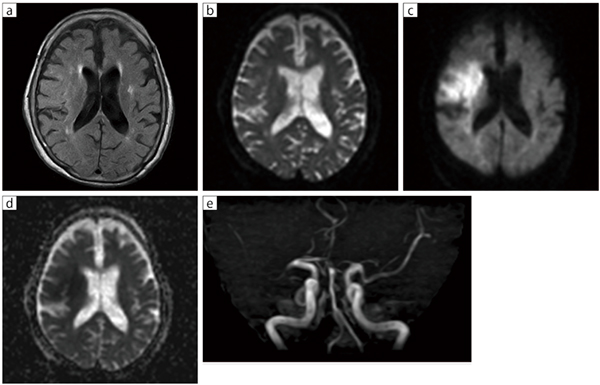

■症例1:右中大脳動脈閉塞

80歳代,女性,救急搬送例。失語症状が見られ,認知症やてんかんも疑われたが,MRIで右中大脳動脈閉塞が確認されたため,すぐに近隣病院へ転送。転送から約50分で血栓回収を実施することができた。

a: FLAIR(RADAR),TR/TE/TI=11865/75.0/2000,スライス厚:6.0mm,スライス枚数:24,FOV:220mm,撮像時間:5:57

b: DWI(b=0),TR/TE=6538/126.8,NSA=8,スライス厚:6.0mm,スライス枚数:24,FOV:220mm,撮像時間:2:57

c: DWI(b=1000),TR/TE=6538/126.8,NSA=8,スライス厚:6.0mm,スライス枚数:24,FOV:220mm,撮像時間:2:57

d: DWI(ADC),TR/TE=6538/126.8,NSA=8,スライス厚:6.0mm,スライス枚数:24,FOV:220mm,撮像時間:2:57

e: MRA(MIP),TR/TE/FA=32.5/7.2/33,スライス厚:1.2mm,IP-Scan=1.1,FOV:160mm,撮像時間:7:08